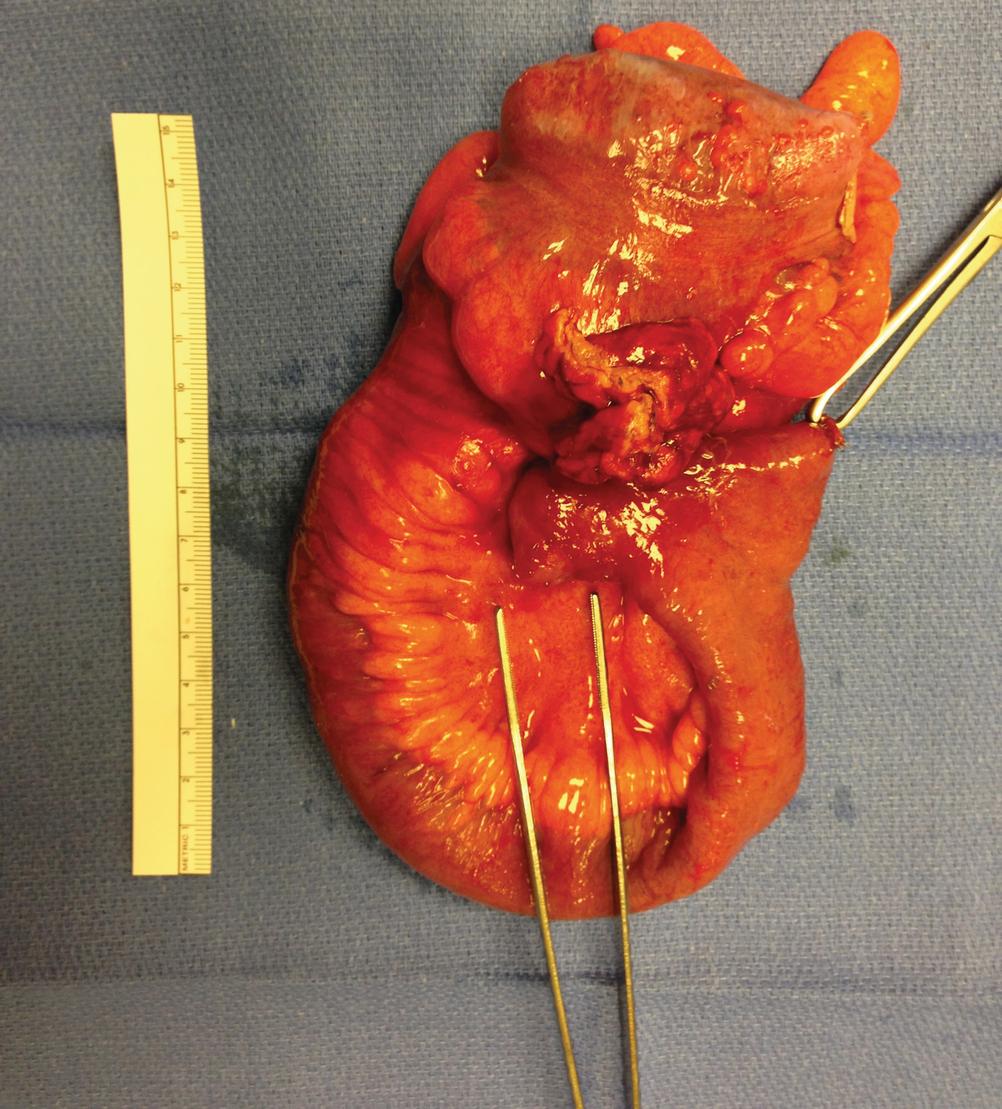

There are three classic anatomic points of differentiation between the colon and the small intestine: the appendices epiploicae, the taeniae coli, and the haustra. The appendices epiploicae are non-mesenteric fat protruding from the serosal surface of the colon. They are likely residual from the antimesenteric fat of the embryologic intestine which dissipates (unlike the omentum on the stomach). The taenia coli are three thickened bands of outer, longitudinal muscle of the colon. This outer layer of muscle is indeed circumferentially complete[60] but is considerably thicker in three areas represented by the taenia. The three taeniae have been given separate names by some: taenia libera to represent the anterior band, taenia mesocolica for the posteromedial band, and taenia omentalis for posterolateral band. The bands are continuous from their origin at the base of the appendix until the rectosigmoid junction where they converge (marking an anatomically identifiable differentiation between the sigmoid colon and rectum). Though they run along the full length of the colon, they are not as long as the bowel wall. This difference in length results in outpouchings of the bowel wall between the taenia referred to as haustra. The haustra are further septated by the plicae semilunares.